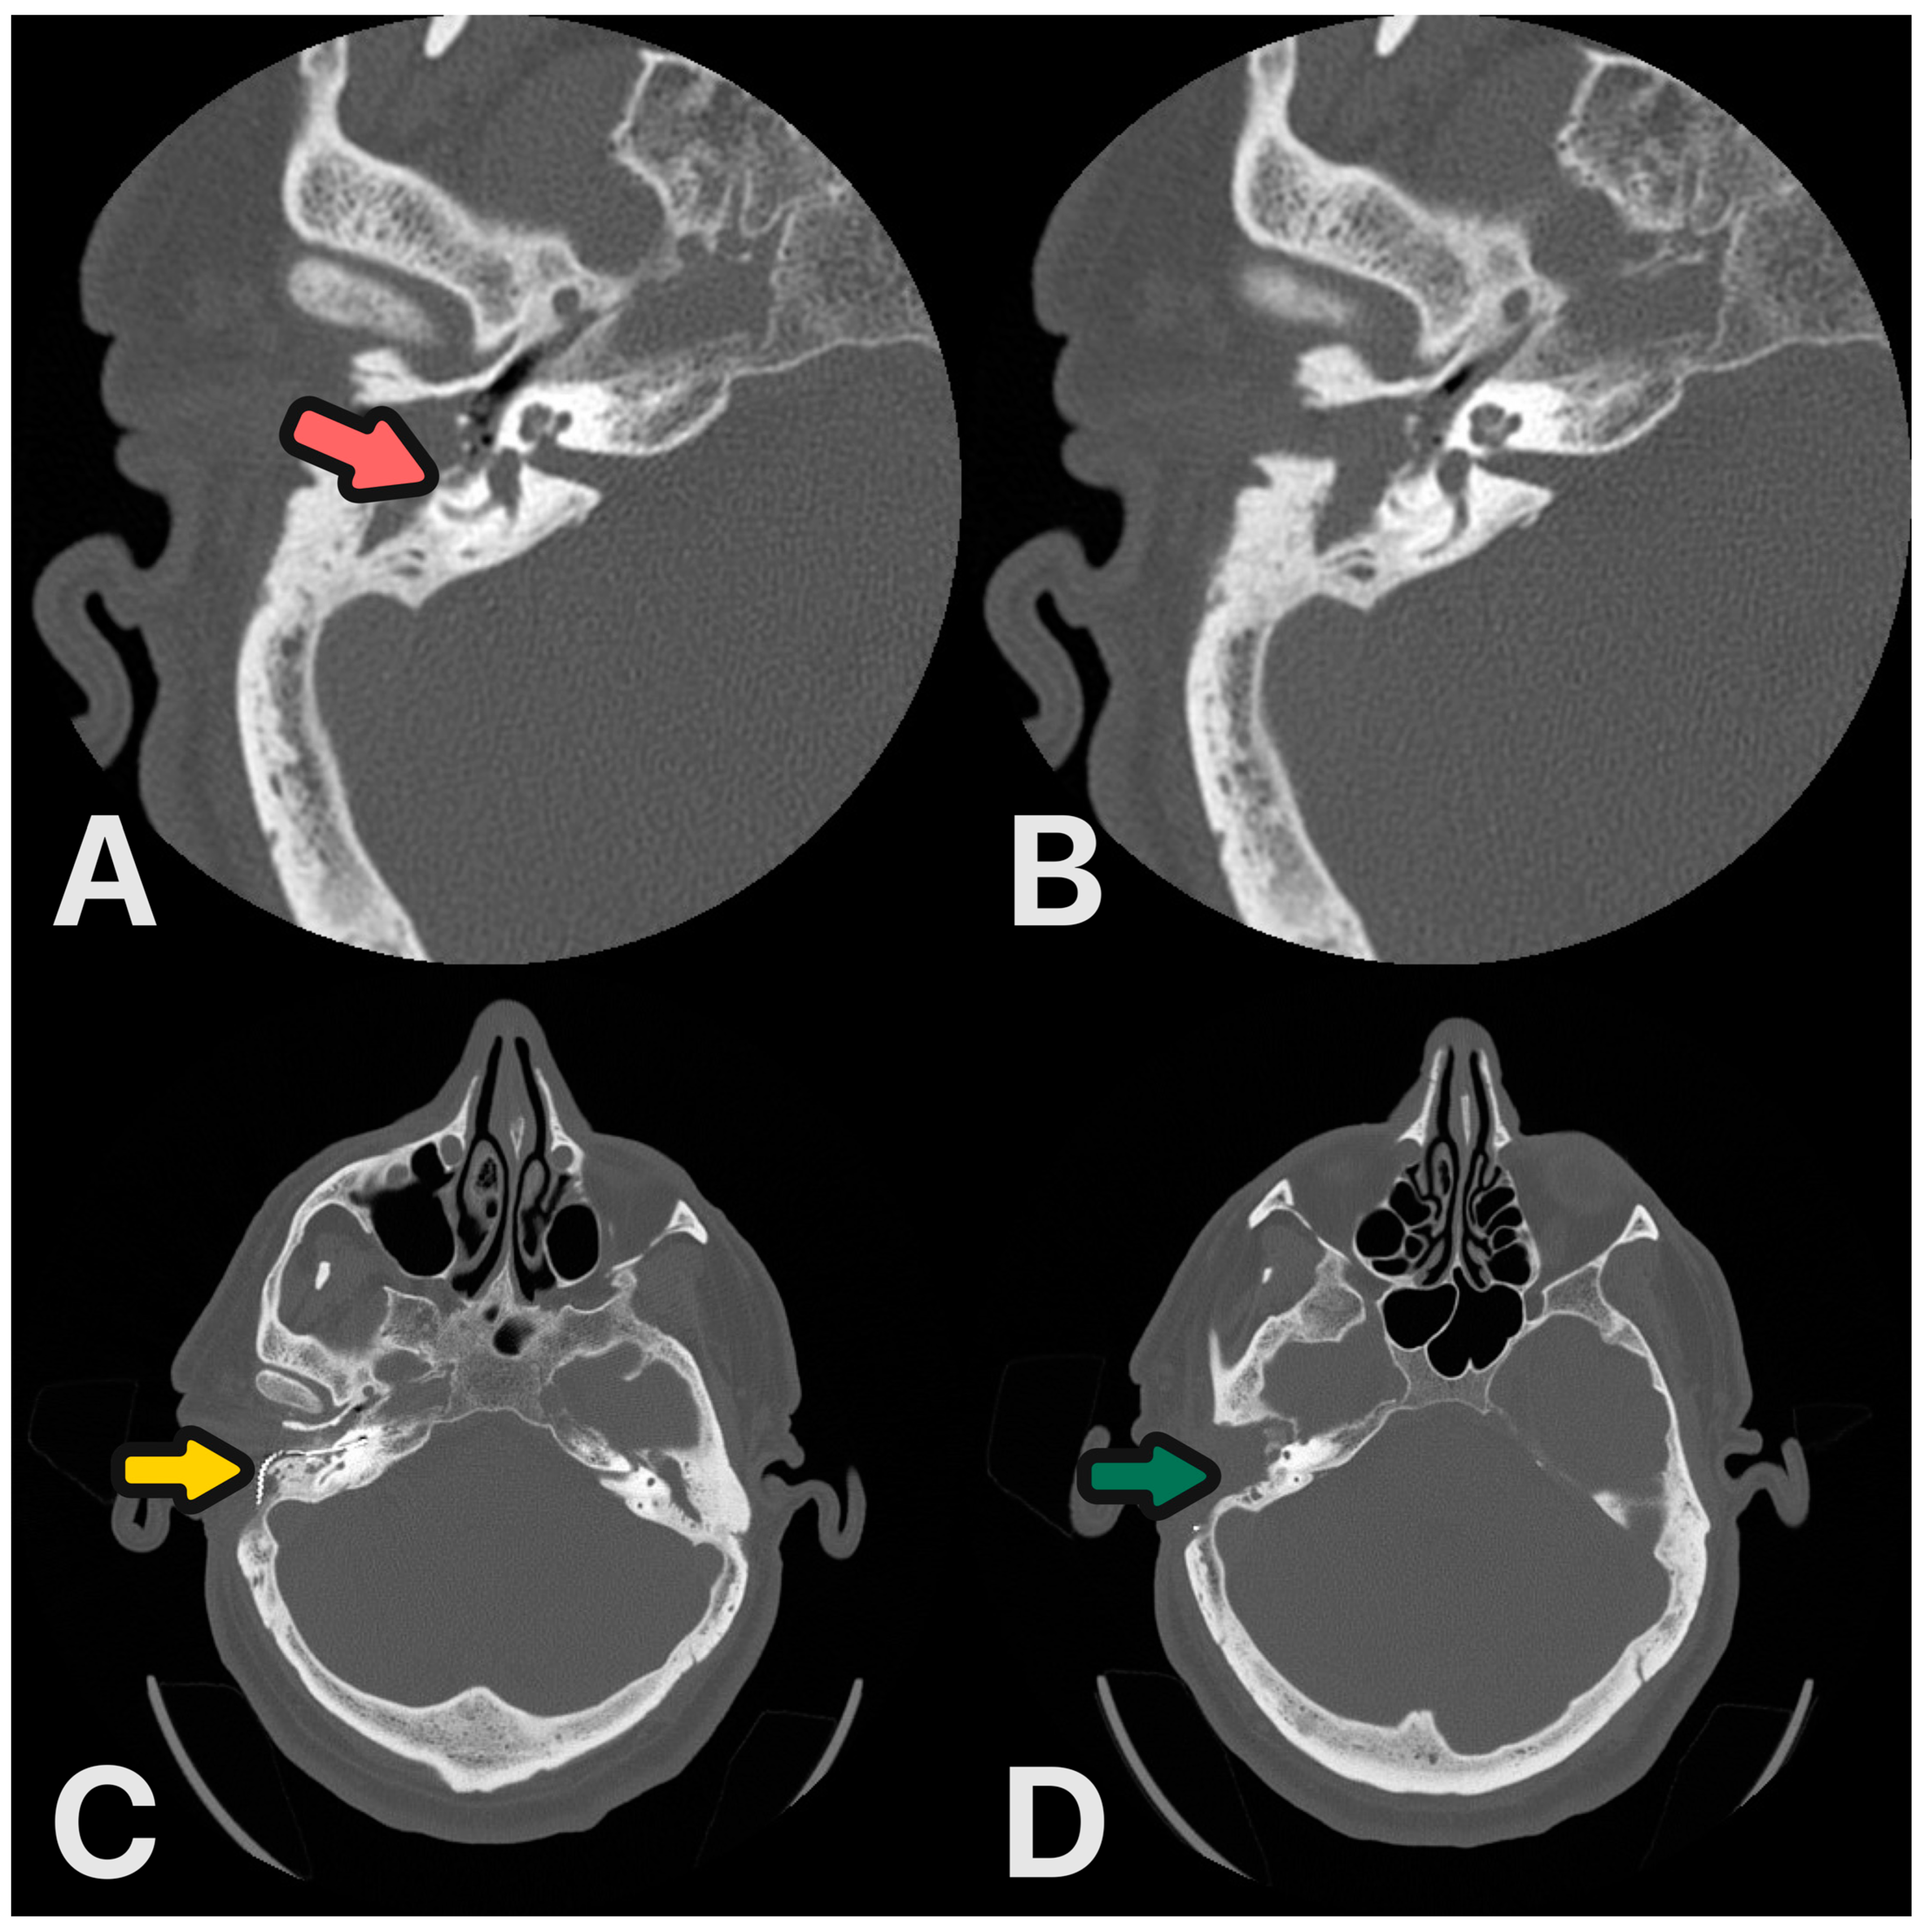

Figure 7.

(A,B) HRCT scans before surgery: destruction of the lateral semicircular canal and posterior canal wall—magenta arrow. (C,D) Control HRCT scans 6 months after procedure: CI electrode—yellow arrow, ear obliterated—green arrow.